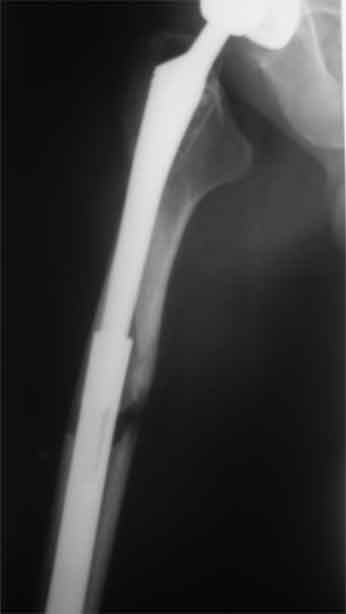

Re: Перипротезный перелом

новые снимки